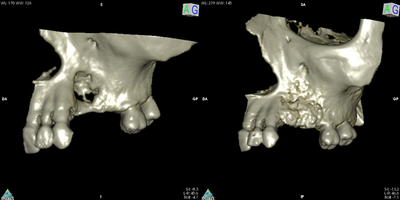

reconstruction osseuse préimplantaire

greffe d'apposition

augmentation osseuse en largeur